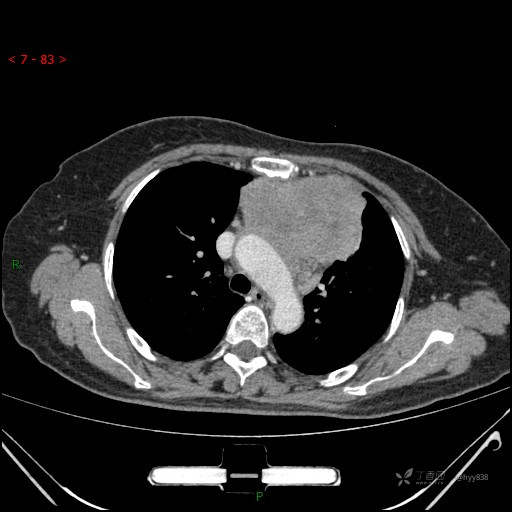

简要病史:患者诉3月余前患新冠肺炎,出现持续性胸闷,活动后可缓解,无胸前区压榨感,无畏寒发热不适,无胸痛咯血、呼吸困难,无恶心、呕吐,无腹痛、腹胀、腹泻等不适,未予以重视,未行特殊处理。患者胸闷持续存在,为进一步诊治,3天前于本院查胸部CT提示前纵膈团块状软组织密度影,肿瘤性病变可能,心包积液,左上肺磨玻璃结节,右下肺增殖灶可能建议进一步检查。门诊以“前纵膈占位” 收入我科。 患者本次起病来精神、食欲、睡眠尚可,大小便正常,体力、体重无明显变化。

辅助检查:CT

穿刺